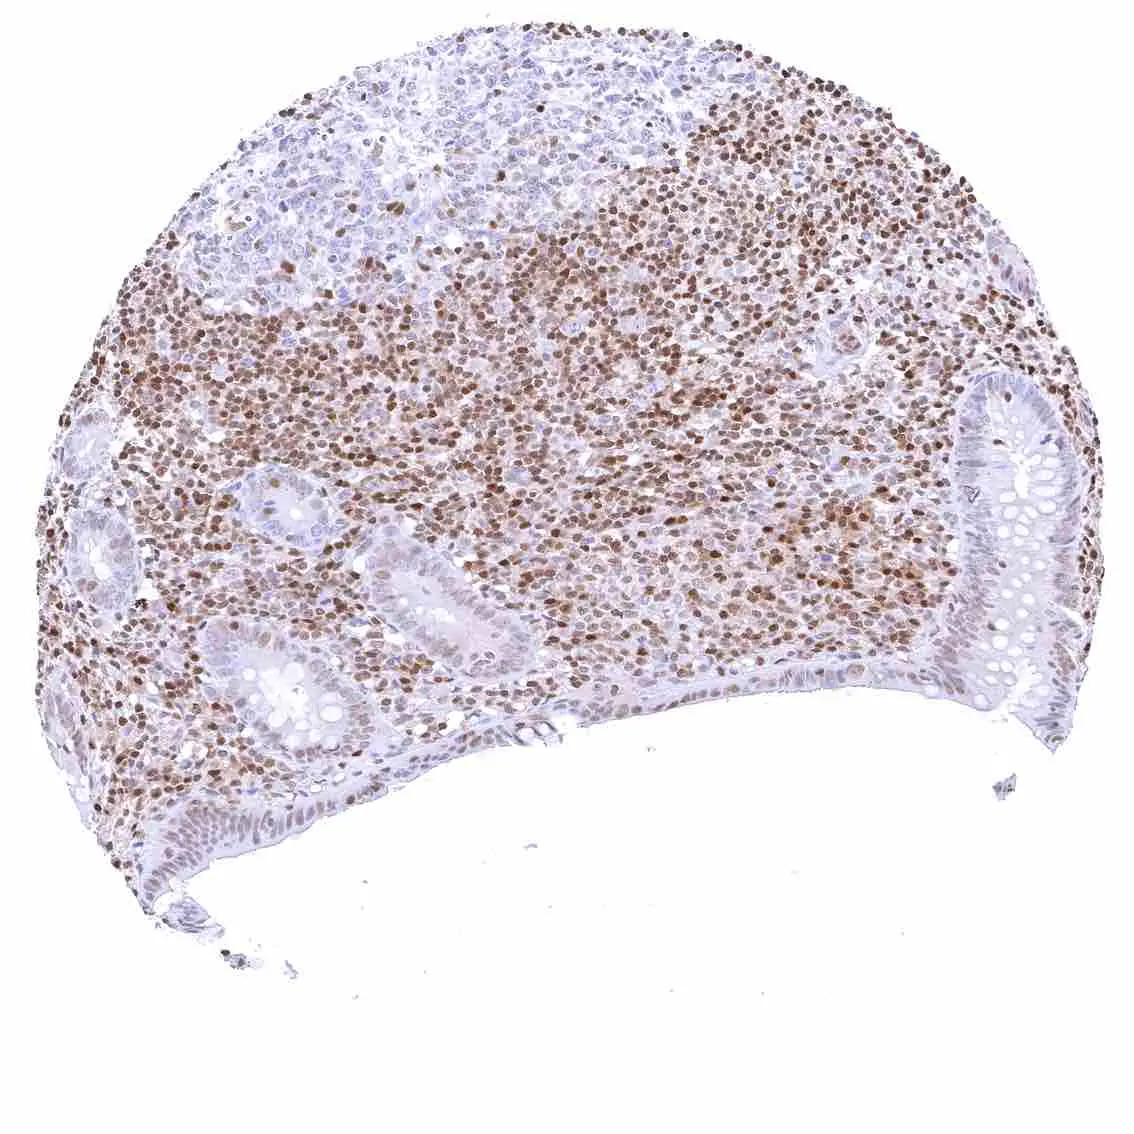

Lymph node – Strong nuclear p27 staining of a significant subset of cells, especially in the interfollicular area.